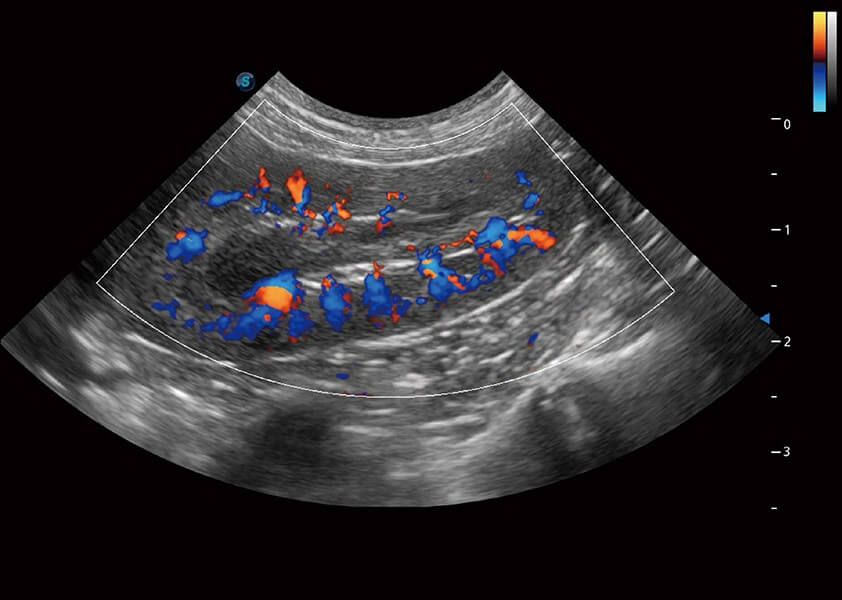

ProPet 60 作为一款高端台式动物超声设备,为动物医生的日常诊断提供了一系列贴合动物临床需求、解决临床实际问题的高级成像功能。凭借全系列高清探头,满足医生对腹部、心脏、生殖、浅表、肌骨等成像的所有需求,切实帮助您提升检查效率,提高诊断信心。

动物是人类最亲密的朋友和最值得信赖的伙伴。milan米兰也一直致力于探索动物专用的超声影像解决方案。 全新推出的ProPet系列,是milan米兰在动物超声影像智能化、专业化、精准化的一次跨越式革新。动物不能用言语来表述自己的不适,通过超声影像,ProPet系列搭建了动物医生与不同物种沟通的“桥梁”,为动物医生注入了“治愈之力”。